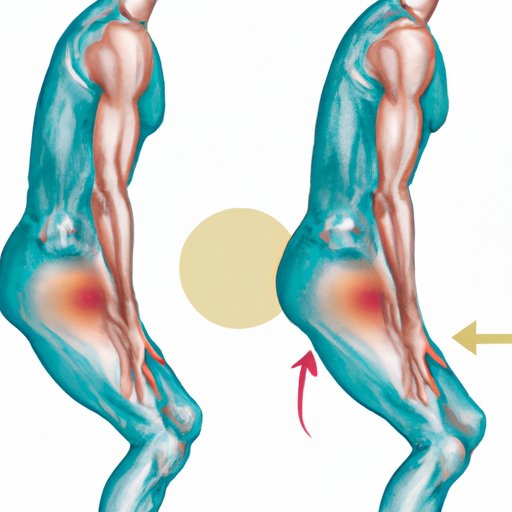

How to Heal a Hamstring Strain Fast: Tips and Techniques

Learn effective techniques to heal your hamstring quickly and get back to your game. Discover the benefits of rest, ice, gentle stretching, massage therapy, heat therapy, exercise rehabilitation, and acupuncture.